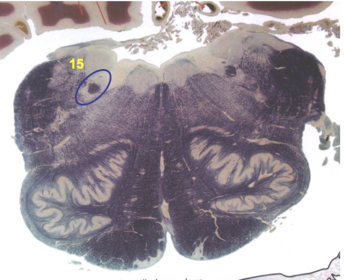

| Medullary pyramids | |

| Hypoglossal nucleus | |

| Hypoglossal nerve | |

| Dorsal motor nucleus of X | |

| Nucleus ambiguus | |

| Solitary tract | |

| Solitary nucleus | |

| ALS | |

| Medial lemniscus | |

| Medial longitudinal fasciculus | |

| Anterior spinocerebellar tract | |

| CN IX | |

| Inferior cerebellar peduncle | |

| Inferior olivary complex | |

| Dorsal cochlear nucleus | |

| Inferior vestibular nucleus | |

| Medial vestibular nucleus | |

| Spinal nucleus of V | |

| Spinal tract of V | |